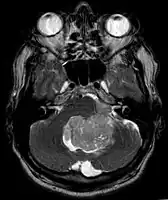

Ependymoma of 4.ventricle in MRI.

Ependymoma of 4.ventricle in MRI. Left without, right with contrast-enhancement.